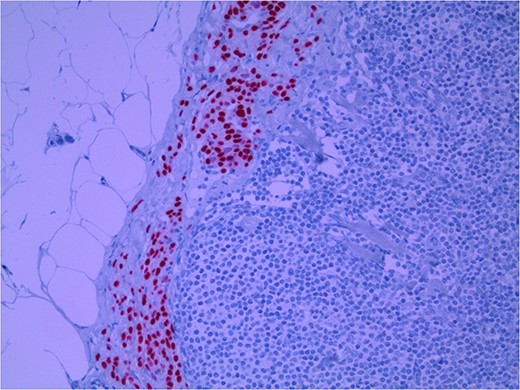

Lymph node specimens were sent for haematoxylin and eosin (H&E) staining (Fig. 3) and IHC analysis. The sections showed mild reactive changes and benign intracapsular nevoid rests. IHC analysis showed that these cells were negative for HMB-45 (Fig. 4) and were positive for both Sox10 and p16 (Figs 5 and 6). Consensus at the Multidisciplinary Team Meeting was that the appearance was in keeping with benign naevoid rests as opposed to melanoma deposits, given the location of the cells, morphology and immunohistochemistry. Surveillance was recommended.

Lymph node with IHC using HMB-45 stain, not staining subcapsular region melanocytic cells; × 200 magnification.

Several IHC stains are in use in the pathological interpretation of primary lesions and SLN biopsies. The antibody HMB-45 reacts with most melanomas. In a primary lesion, HMB-45 is immunoreactive with intraepidermal and superficial dermal components of benign nevi [14]. In a lymph node, however, benign nevoid cells are negative for HMB-45 and appear bland. A loss of HMB-45 expression has been reported in 20% of melanocytic metastasis, illustrating the need for further diagnostic testing [14]. Sox10 is a nuclear transcription factor that stains benign and malignant melanocytic cells. It indicates the extent of melanocytic spread but does not differentiate between benign nevi and metastatic melanoma [15]. Immunostaining for the tumour suppressor gene p16 differentiates between benign naevi and melanocytic metastases in the SLN. One study demonstrated positive nuclear and cytoplasmic p16 staining in all nevi (dermal and lymph node) and the absence of nuclear p16 staining in all but one melanoma metastasis [14]. No single stain is completely sensitive for melanocytic metastases, and a confident diagnosis relies upon cell location, morphology and multiple IHC techniques. SLN biopsy in the current patient demonstrated intracapsular melanocytic cells which stained negative for HMB-45, and positive for Sox10 and p16, in keeping with benign nevoid rests as opposed to metastatic melanoma.